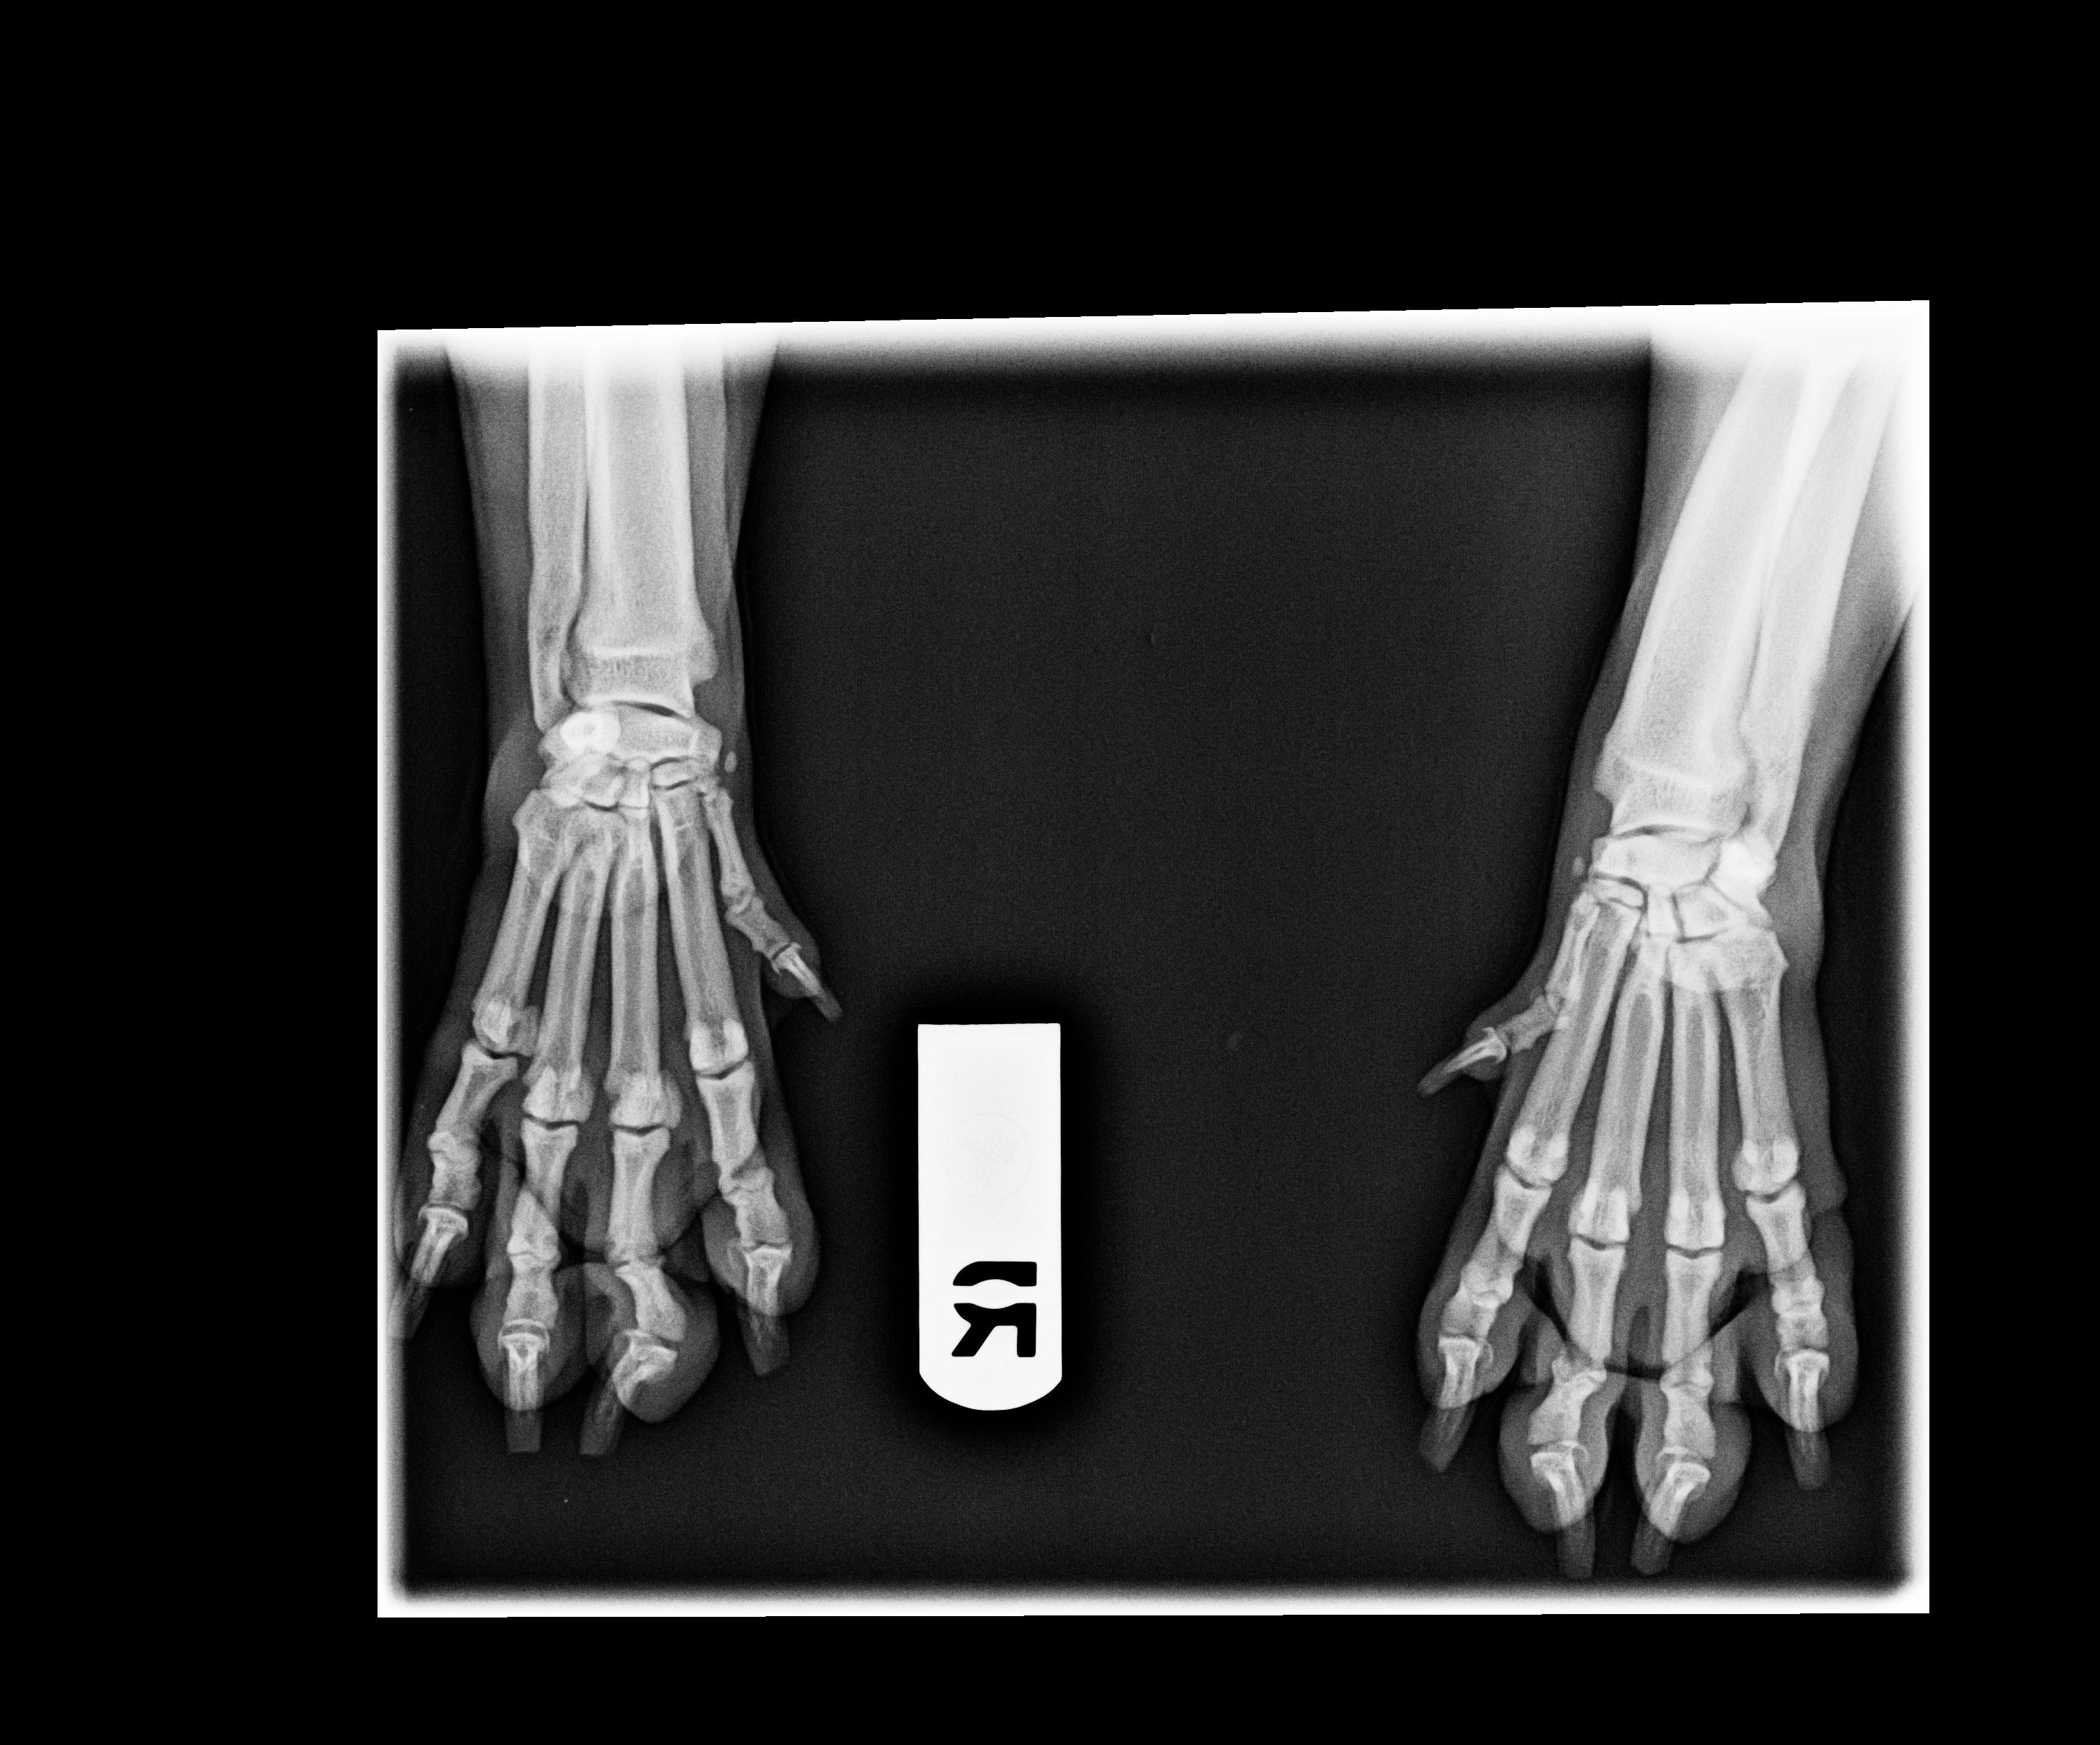

They did the xrays today. Two doctors looked at them, and they don't see anything irregular. They did make note of a small shadow on the elbow, but the doctor said that it could be nothing. The xrays were sent to the radiologist, who will review them and have a better diagnosis. I feel really good about getting the xrays. If nothing else, it gives me peace of mind. It crushes me when I see her limp. She's just a baby! Anyway, knowing that we had xrays done will keep me from thinking it's something terrible.

They should have the radiologists thoughts within a day or so.